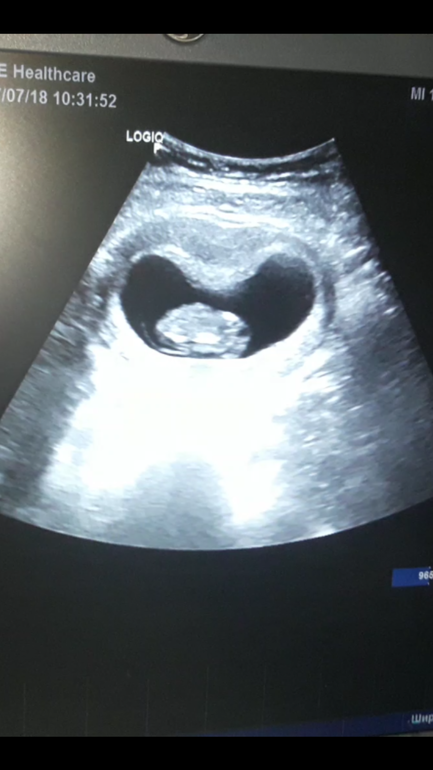

10 неделек)))) Фото ниже)))))

Сегодня после лапары было контрольное узи))) мы растем вопреки всему! КТР 32)))

Видела с экрана как манюся шевелит головкой, ручками и ножками! Эмоции посто зашкаливают.

Класс, у нас такой же КТР был на последнем УЗИ! Растите здоровенькими ❤️